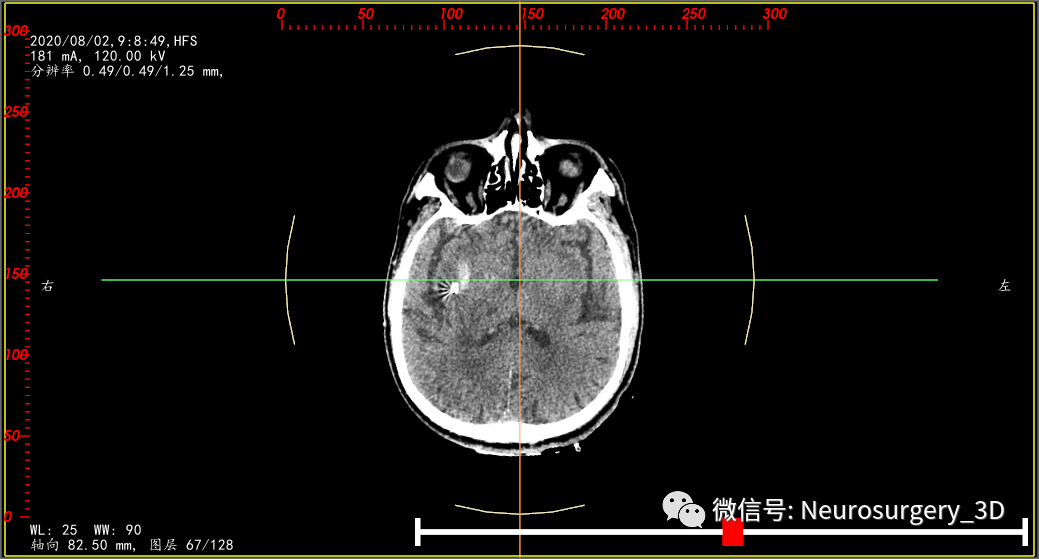

术后第一天复查CT后应用尿激酶一次,2020年8月2日CT复查后给予拔除引流管。

再来一例病例(2020年8月5日9:39)入院,王友某,男,61岁,入院时CT,也是高低密度分层,像不像活动性出血?

微创钻孔置管引流术后4小时CT复查(引流管位于血肿中心)